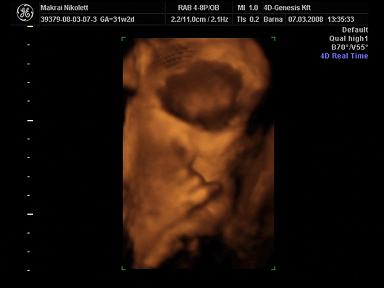

2008.03.07 20:04